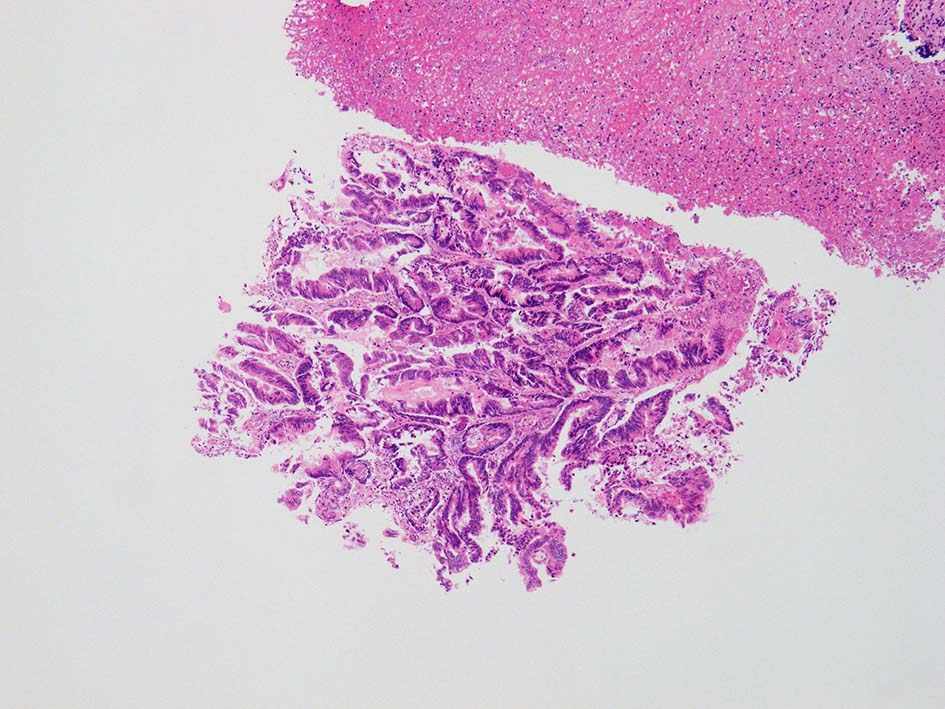

膀胱原発腺癌は隣接臓器, 特に結腸に発生する腺癌と診断上混同される。組織学的には, 様々な組織学的パターンを伴う大腸(腸)型腺管形態が優勢である。形態学的特徴から大腸型腺癌(not otherwise specified)、粘液性、印環細胞型、透明細胞型、肝細胞型、混合型に分類される。*3*4

腸管型の腺癌。大腸の高分化腺癌と組織学的に区別は難しい.

GI tract, とくに大腸癌の膀胱浸潤/転移を最初に考えた.